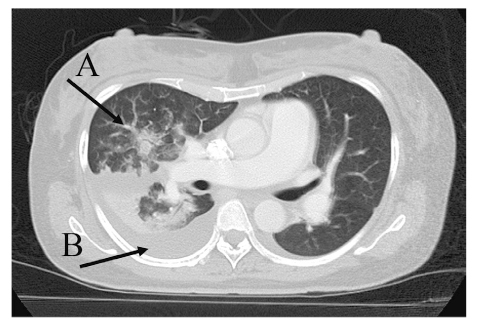

The incidence of Acinetobacter infections has increased in recent years. Acinetobacter infections are resistant to most antibiotics and can be found in hospitalized patients. Pregnancies complicated by severe sepsis or septic shock are associated with a higher rate of preterm labor and delivery, fetal infection, and operative delivery. This case report describes septic shock due to Acinetobacter lwoffii infection in the 31st week of gestation. A 47-year-old woman, with a gestation of 31 weeks and one day, presented with a fever, and signs of bacterial infection on laboratory tests. Although the patient was started on tazobactam/piperacillin, she went into septic shock, and was transferred to our hospital. Cesarean section was performed at a gestation of 31 weeks and 4 days because of severe maternal pneumonia and non-reassuring fetal status. A. lwoffii was detected in blood cultures collected at the previous hospital, and susceptibility to piperacillin and meropenem to A. lwoffii was confirmed. The pneumonia responded to antibiotic treatment and there were no findings of infection in the neonate. Maternal sepsis is an infrequent but important complication, causing significant maternal and fetal morbidity and fetal and neonatal mortality; therefore, early antibiotic therapy is required to improve the clinical outcome.

Abstract Image